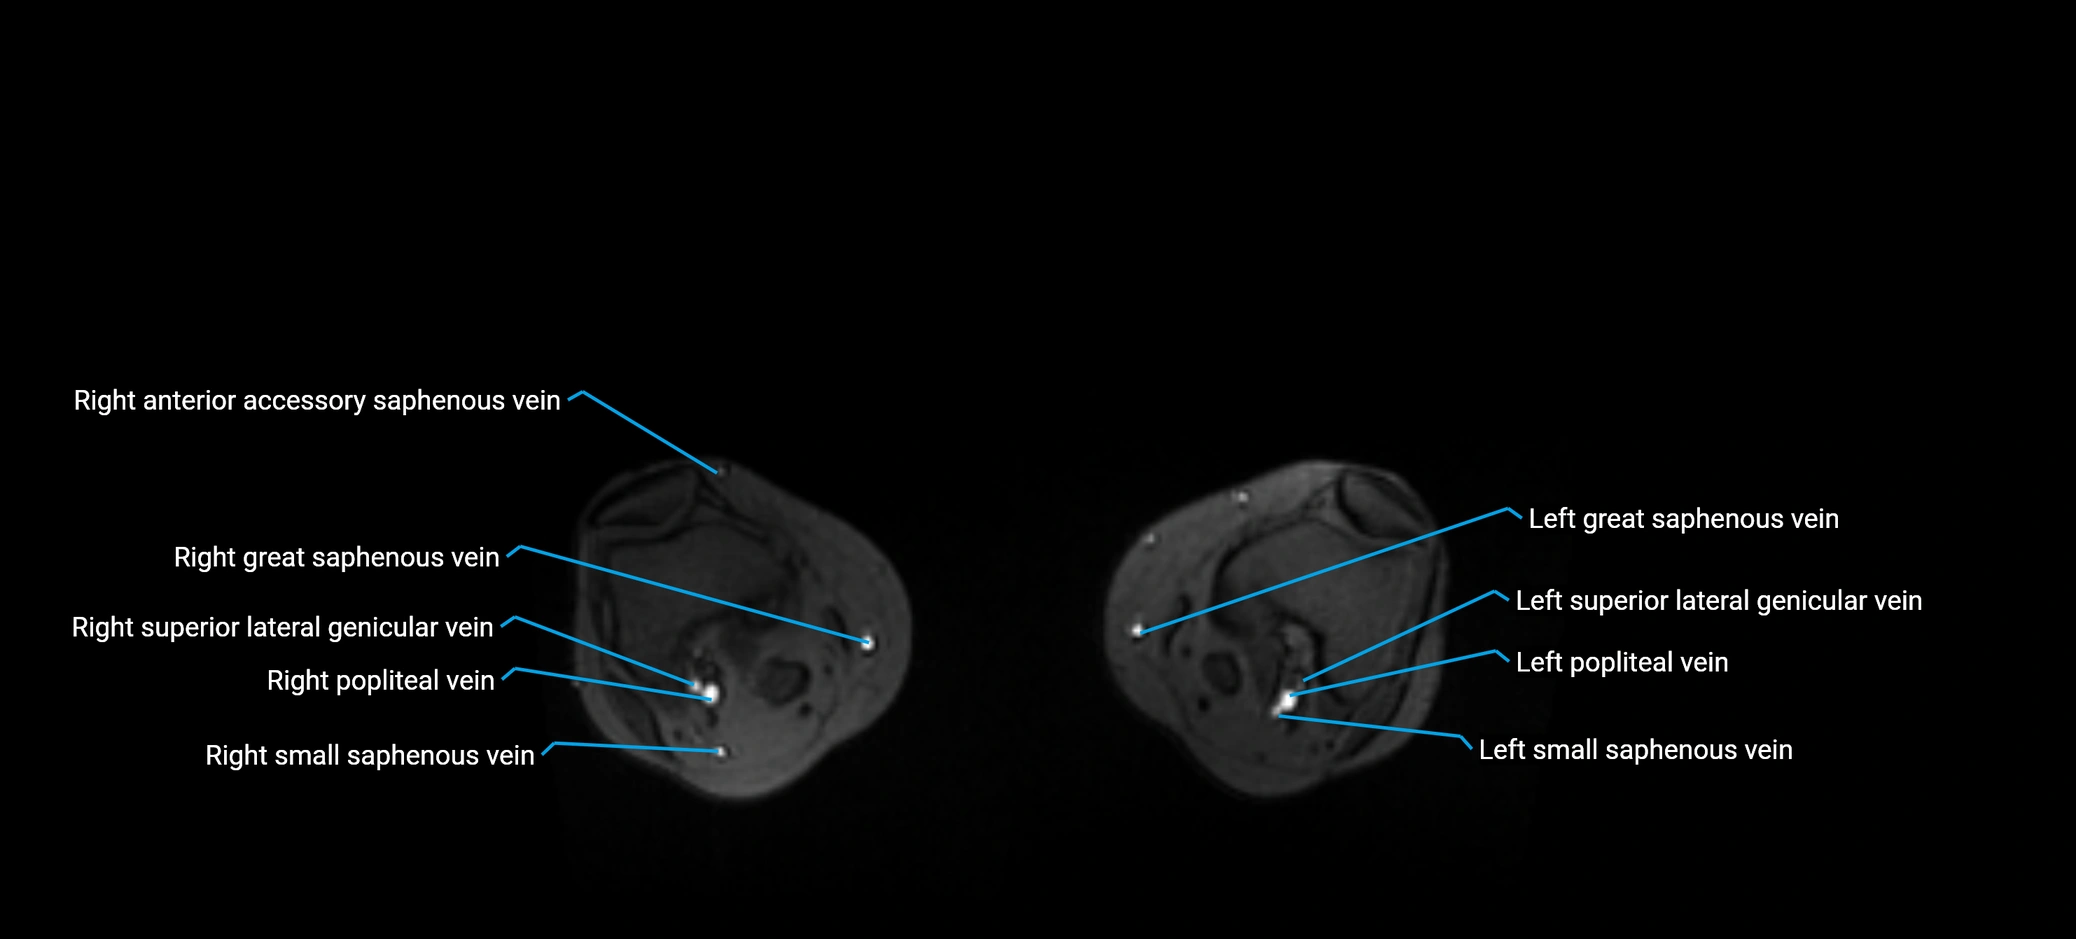

MRI image

image